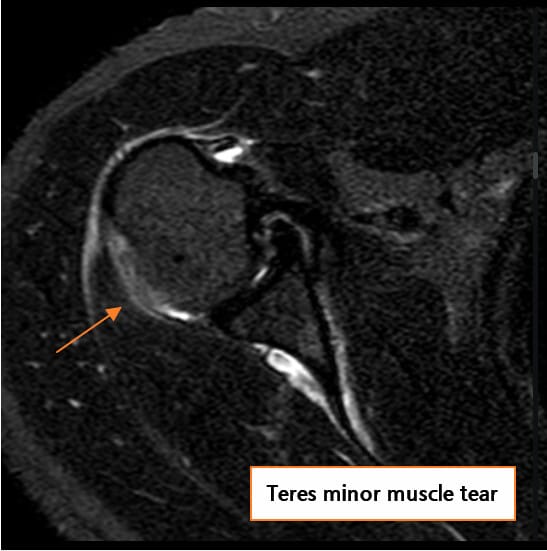

MRI (자기공명영상)

회전근개 힘줄의 부분 또는 완전 파열 여부, 파열 크기, 주변 근육의 지방 변성 및 위축 소견을 확인할 수 있습니다. 액체 음영이 파열 부위에 고여 있는 소견(fluid-filled gap)이 특징적입니다.